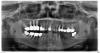

eva-hao Опубликовано 6 августа, 2013 Поделиться Опубликовано 6 августа, 2013 Уважаемые доктора, нужен совет по сложившейся ситуации на нижней челюсти. Несколько лет назад были удалены 36 и 37, взяты под коронки 34 и 35, и сделан бюгельный съемник на замках. Теперь уходят 34 и 35 и встаёт вопрос о дальнейшем протезировании. Меня интересует вопрос, возможно ли это сделать? Доктор предлагает поставить 3 импланта и 4 коронки на мостике. Но у меня есть подозрение, что в обл. давнего удаления 6 и 7 кость убыла достаточно в приличном количестве. Что можно сделать, что бы импланты не вывалились, если всё -таки рассматривать этот вариант протезирования? Ссылка на комментарий

M@estro Опубликовано 7 августа, 2013 Поделиться Опубликовано 7 августа, 2013 (изменено) Судя по снимку,справа снизу тоже не все гладко,если судить только о нижней челюсти. Изменено 7 августа, 2013 пользователем M@estro Ссылка на комментарий

red_butler Опубликовано 7 августа, 2013 Поделиться Опубликовано 7 августа, 2013 А справа с 6-кой проблема? И какие перспективы? Я попробую вылождить кт, но наверное это займёт время. В любом случае, спасибо за ответы.Внизу справа проблемы с зубами 4.8 4.7 4.6 4.5. 4.8 и 4.6 удалять, с остальным разбираться Ссылка на комментарий